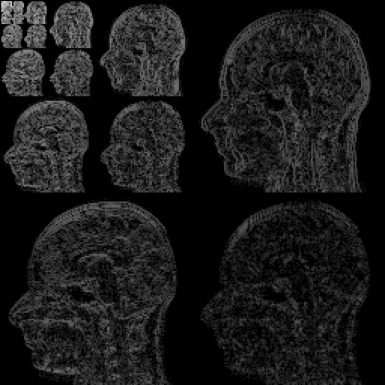

We present some numerical examples in Figure 12, where we compute solutions of the optimization problem (3.36). In this example, the neural network simulating the Bloch map is trained via a training set which was obtained through discrete dynamics of simulated Bloch data. In particular, a set of parameter pairs in the feasible domain of and is taken as inputs of the network, and then the simulated Bloch dynamics resulting from all these pairs are regarded as the outputs. The simulated k-space data in this example are generated using exactly the same setting as the one used for Figures 3 and 4. For such a discrete time series, the Bloch map is a Nemytskii type operator, and thus can be approximated sufficiently well in a uniformly bounded feasible set.